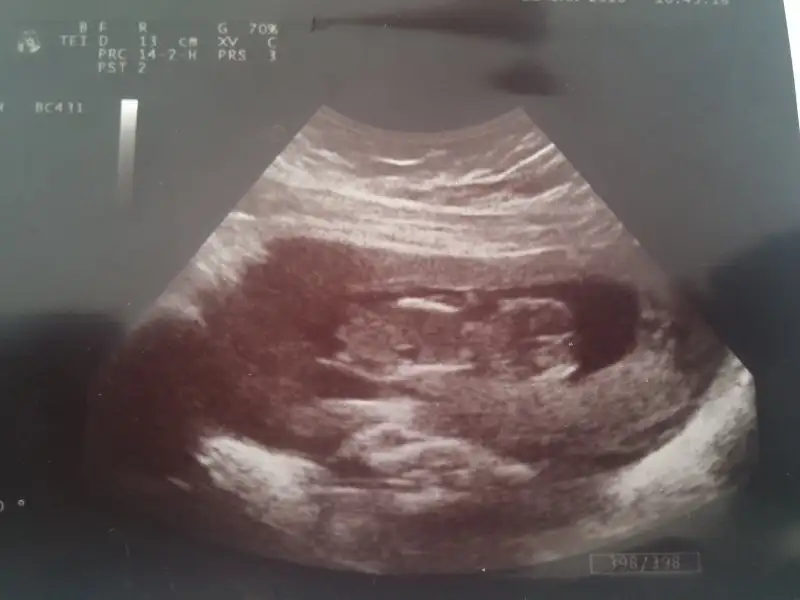

bu da benim bebişim kızlar bakarmısınız benimkide fasülye gibi ama uzunlamasına.ve bebişte altta görünüyor nasıl yorumlarsınız

Arkadaslar benim bebeğim 7+3 haftasında ortada duruyor sizce cinsiyeti nedir?? Tahminde bulunursanız sevinirim :KK76:

Eklentiler

• image.webp

image.webp

16,7 KB · Görüntüleme: 89